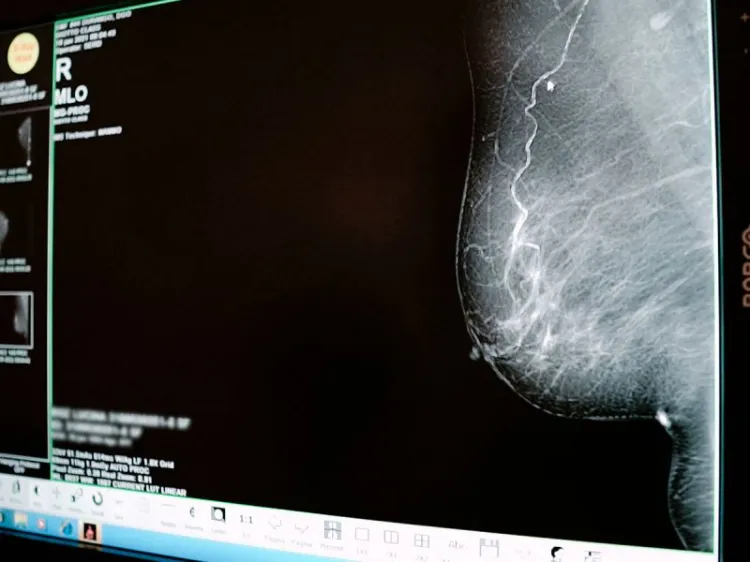

Cáncer de mama: Autoexplórate, esta práctica puede salvar tu vida

En lo que va del 2021, el Instituto Mexicano del Seguro Social (IMSS) de Durango, informó que se han diagnosticado 19 nuevos casos de cáncer de mama, por lo que invitó a mujeres y hombres a realizarse la autoexploración ya que practicarla con frecuencia puede salvar vidas.Norma Angélica Lamas Nolasco, coordinadora de Prevención y Atención a la Salud del IMSS, sostuvo que este padecimiento se ha incrementado y su aparición cada vez se presenta en edades más tempranas, por lo que el IMSS exhorta a las mujeres a llevar a cabo la autoexploración y el chequeo constante para detectar oportunamente alguna tumoración maligna.Destacó que el cáncer de mama es actualmente uno de los principales problemas de salud y muerte en la mujer mayor de 40 años.Sugirió que la autoexploración puede ser después del séptimo día del periodo de menstruación, de la siguiente manera: estando de pie se debe colocar la mano derecha en la nuca y con la izquierda tocar el pecho derecho.Comienza desde arriba palpando alrededor de la mama y luego en la parte del centro. Posteriormente, revisa toda la axila y al final aprieta el pezón para ver si hay salida anormal de líquido. Después, explorar el otro seno de la misma manera.Lamas Nolasco invitó a la población femenina que tenga antecedente familiar de cáncer de mama, a acudir a su Unidad de Medicina Familiar (UMF) para que el personal de PrevenIMSS actúe para una detección oportuna.